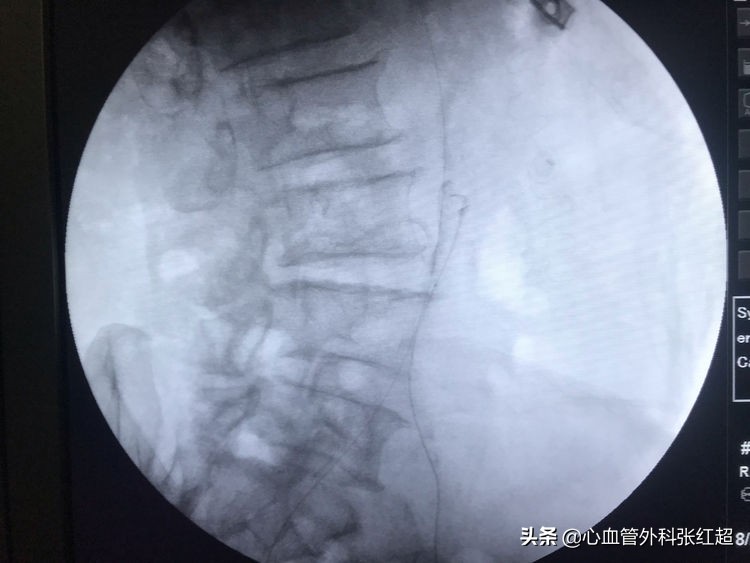

导丝进入假腔方向,加用微导管,换导丝破膜入真腔。

方位验证导丝入真腔后,用微导管造影进一步验证。

送入小球囊扩张,目的:①预防出血;②预防血栓脱落。

扩张时一定注意保持外鞘位置,避免血肿形成。